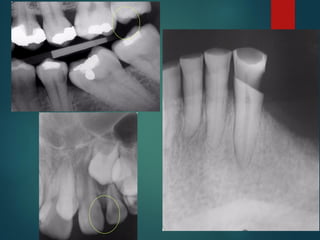

 Incipiente de esmalte

 De esmalte

 Dentinaria superficial

 Dentinaria profunda

 Sobreproyectada en cámara pulpar

 Penetrante

Clasificación Radiográfica

De Las Caries